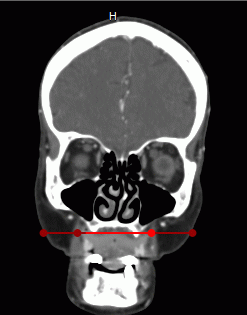

In the Involute window, a straightened curve and perpendicular cutting planes projections are shown. When you mouse over a cutting plane in the Involute window, the respective plane and projection will be highlighted. The point in which the cutting plane crosses the curve will be marked with a crosshair in the slices window.

To rotate the surface round the curve, mouse over the Involute window and scroll the mouse wheel or move the slider in the slices window.

To move the cutting planes along the curve, mouse over the slices window and scroll the mouse wheel or move the slider in the slices window.